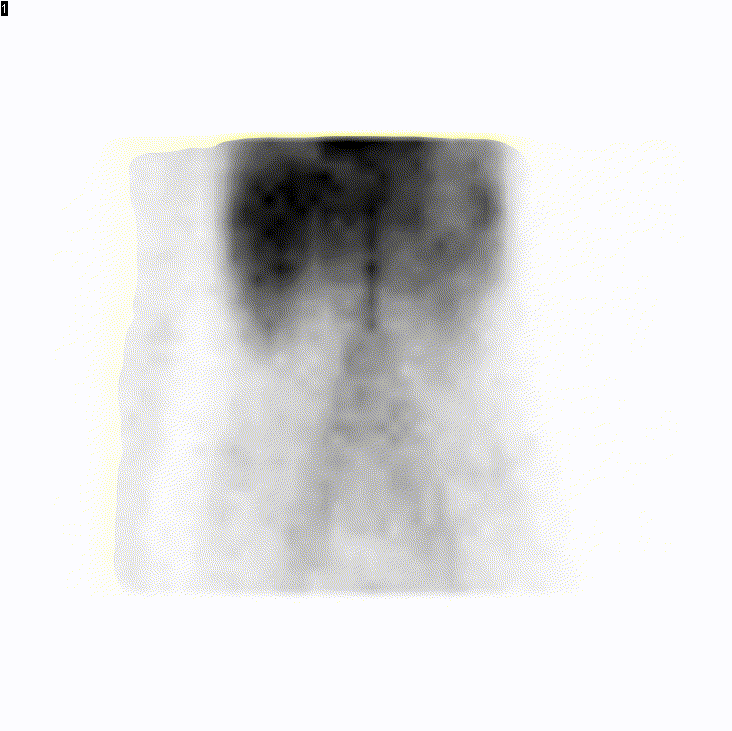

Garçon de 14 ans. Bilan de rectorragies et méléna.

Examen : scintigraphie au Technecium

Préparation : administration de Pentagastrine avant l’examen

Diagnostic : hyperfixation focalisée en fosse iliaque gauche d’apparition simultanée à l’estomac : diverticule de Meckel avec hétérotopie gastrique responsable d’une hémorragie digestive.

Une acquisition TEMP/TDM pourrait être utile pour préciser la localisation exacte du diverticule.

Dans notre cas le diverticule de Meckel avec muqueuse gastrique ecotpique était suspecté devant un antécédent de premier épisode de saignement digestif à 2 ans avec bilan négatif. L’examen a été demandé à 9h, j’ai tout de suite fait monter dans le service de pédiatrie un 1/2 cachet de 300mg de ranitidine , nous avons fait l’examen à 10h avec un succès total de la préparation.

J’ai fait une TEMP/TDM (tdm low dose) qui à posteriori n’était pas utile : je voulais être sûr qu’il ne s’agissait pas d’un foyer urinaire avant de l’envoyer au bloc mais on peut voir sur les dernières images dynamiques que le foyer bouge avec le péristaltisme. La tomo localisait le saignement sur une anse iléale, le diverticule de Meckel avec muqueuse gastrique ectopique a été confirmé sur pièce.